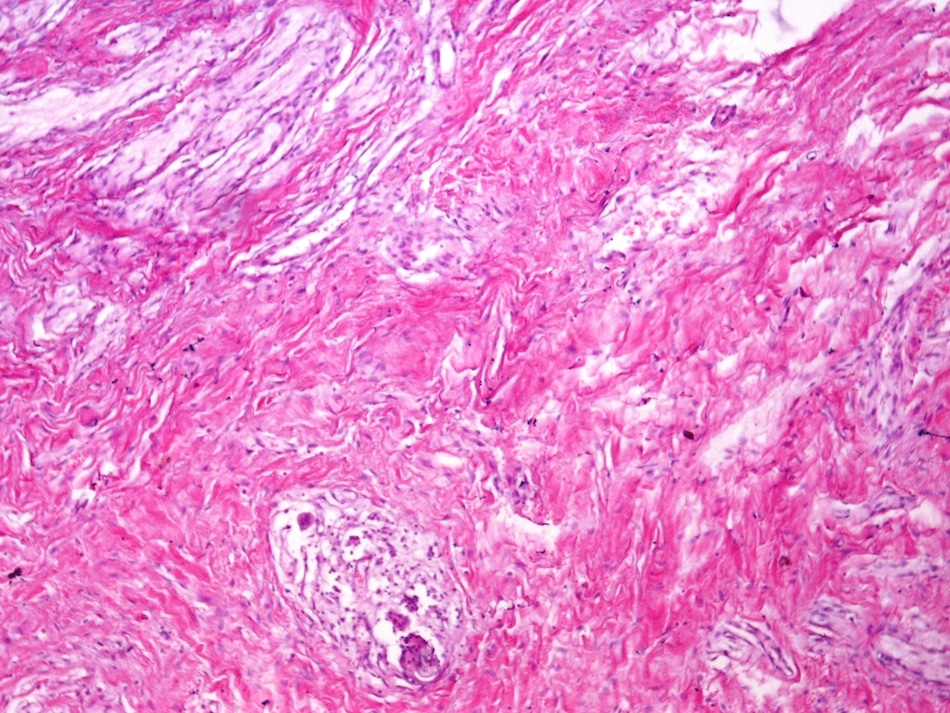

Microscopic images:

Both cases showed disorganized and thickened nerve bundles composed of spindle shaped cells, without atypia. Case A also showed a focal foreign body type giant cell reaction adjacent to the disorganized nerve bundles and a strongly immunoreactive S100 stain.

Histology typically shows hyperplastic nerve bundles, positive for S100.

Microscopic images:

Both cases showed disorganized and thickened nerve bundles composed of spindle shaped cells, without atypia. Case A also showed a focal foreign body type giant cell reaction adjacent to the disorganized nerve bundles and a strongly immunoreactive S100 stain.

Histology typically shows hyperplastic nerve bundles, positive for S100.